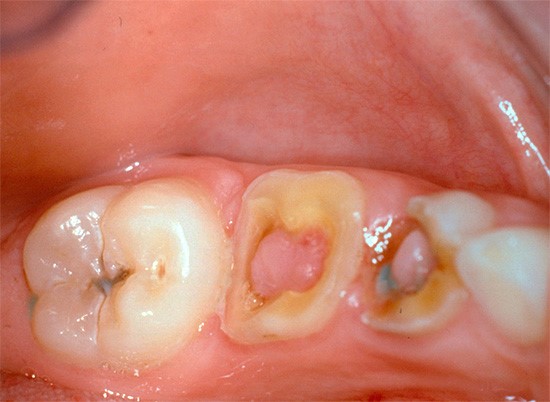

- Характеризуется эта болезнь и глубокой полостью, пораженной кариесом.

В ситуациях, когда полости, пораженные кариесом, находятся в недоступных для внешних раздражителей местах, при этом соединение между полостью, подверженной кариесу и полостью зуба хорошее, а жалобы на боль отсутствуют, заболевание обнаруживается доктором во время осмотра.

Хронический фиброзный пульпит представляет собой воспаление зубной пульпы, которое может развиваться в результате длительного воздействия кариеса или травмы зуба. Врачи отмечают, что основными симптомами являются периодические боли, особенно при воздействии на зуб горячей или холодной пищи, а также возможное изменение цвета зуба. Причинами заболевания чаще всего становятся запущенные кариозные процессы и недостаточная гигиена полости рта.